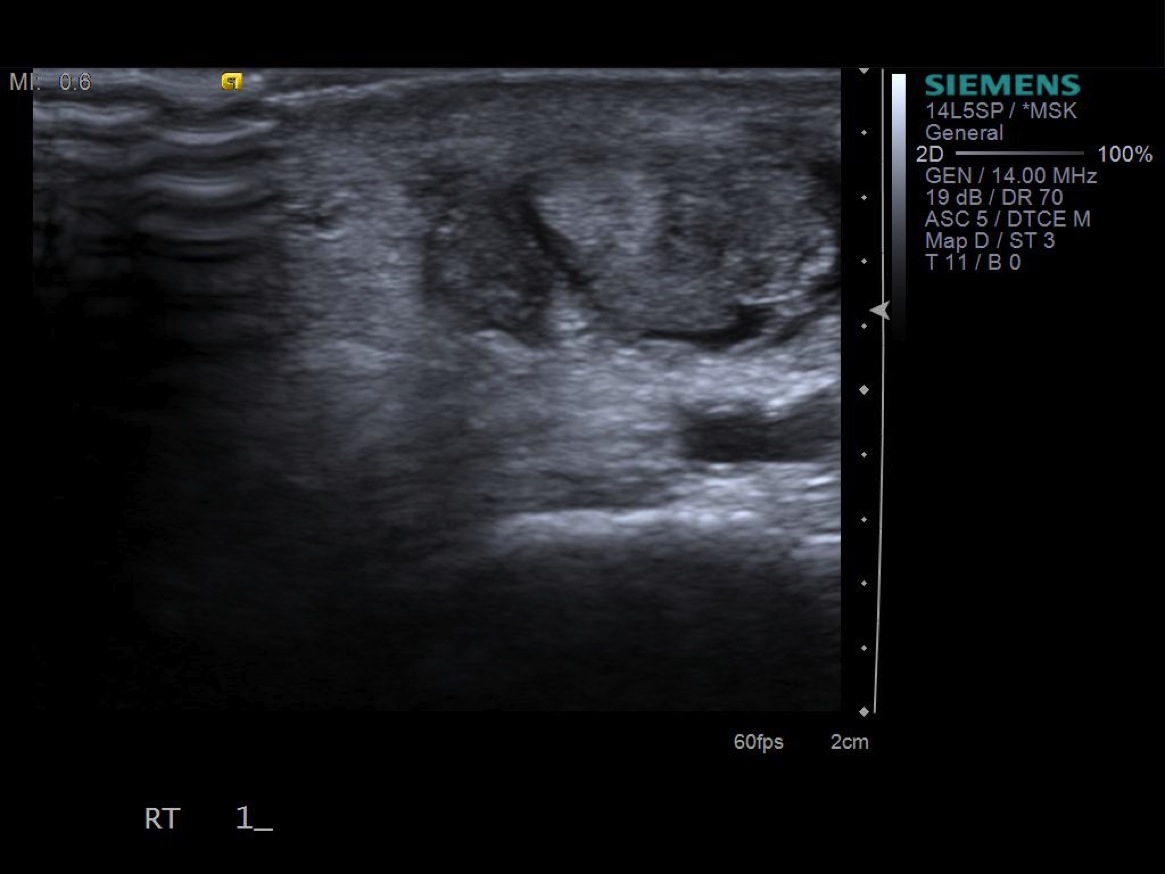

• probe: 14Mhz hockey stick probe

3. Place probe in short axis over first comparment extensor tendons-- Extensor pollicis brevis and abductor pollicis longus. description description

6. Inject 1% lidocaine superficially with 25g 1.5” needle. Advance needle deeper surface of the 1st extensor tendon sheath. Oftentimes, the APL and EPB tendons are in separate sheaths and may require separate injections. Then, unscrew syringe from needle for greater needle control.

7. Under ultrasound guidance,advance needle into the 1st extensor tendon sheath. In this case the APL and EPB have separate sheaths and require their own injections. Test inject with 1% lidocaine. If no resistance, switch 1% lidocaine for injectable steroid mixture. If there is resistance, reposition needle and test inject again. Inject 1 cc of injectable steroid/anesthetic mixture.